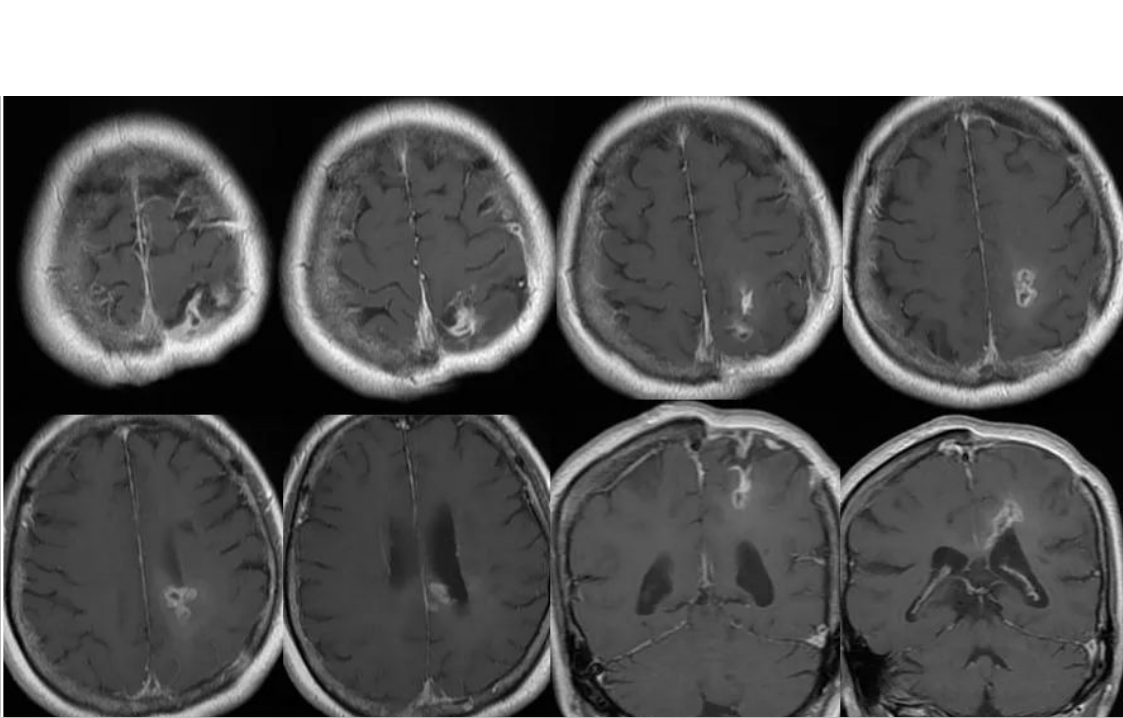

1.磁共振增强:放化疗后可导致血管内皮细胞损伤、坏死,造成血管内皮细胞紧密连接损害,BBB功能损害、通透性增强,在MR增强强化。MR增强上出现强化灶、新强化灶。类似肿瘤复发的影像学表现。胶质母细胞瘤放疗后,MR增强强化见于:70%:肿瘤复发、坏死(结节或多发强化区,术后3月后);30%:单侧放射性坏死(地图样强化)。

肿瘤复发:多发病灶沿白质纤维束播散、累及胼胝体

根据影像学表现和特点,晚迟发反应型可分为无病灶期、水肿期、坏死期、囊变期,各期表现可能同时或先后出现在同一患者脑部的不同部位。

3.坏死期:脑组织病灶局部出现坏死,可伴有出血或渗血,头颅MRI显示信号不均,增强扫描可见强化。